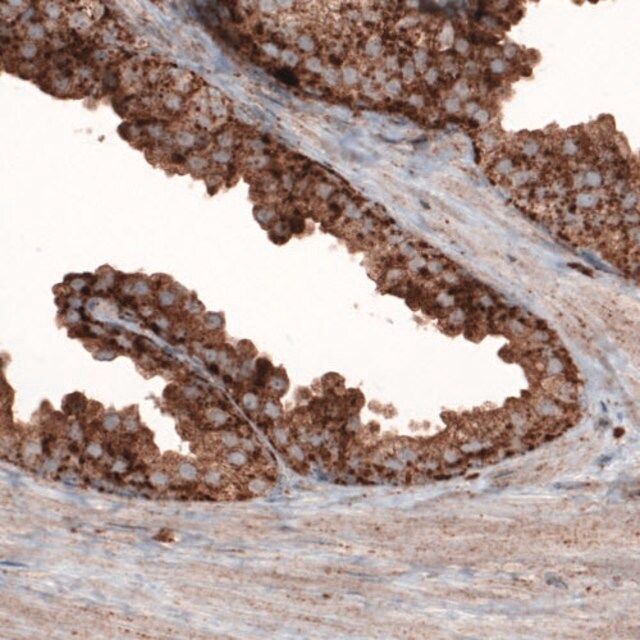

The gene LAMP1 (lysosomal-associated membrane protein 1) encodes a type I transmembrane protein has a short cytoplasmic tail containing a lysosome-targeting signal of GYQTI(382)-COOH. The gene is mapped to human chromosome 13q34.

The gene LAMP1 (lysosomal associated membrane protein 1) encodes a membrane glycoprotein that functions as an intracellular receptor. It is found to be expressed in the cytoplasm of several types of tumor cells and may be involved in tumor invasion. Lamp1 is crucial for perforin trafficking to the lytic granules and motility of these lytic granules. Its knockdown leads to inhibition of cytotoxicity of human natural killer cells.

| technique(s) | immunoblotting: 1 μg/mL immunohistochemistry: 1:5000- 1:10000 |